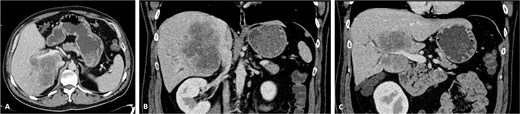

The patient was discussed at a multidisciplinary meeting for suspected intrahepatic cholangiocarcinoma. Due to the tumour size and macrovascular invasion, the patient was proposed for neoadjuvant treatment. After a biopsy confirmed the diagnosis, the patient underwent three cycles of gemcitabine and cisplatin, resulting in a reduction of the cholangiocarcinoma from the maximum longitudinal diameter of 12.6 to 7.5 cm (Fig. 2). An extended right hepatectomy with resection and reconstruction of the PV and IVC using an APFP was then proposed.

CT scan of the intrahepatic cholangiocarcinoma after chemotherapy. (A) Axial CT scan showing cholangiocarcinoma diameter reduction after chemotherapy and (B) and (C) coronal CT scan view of the vascular relation between the cholangiocarcinoma, IVC, and PV.